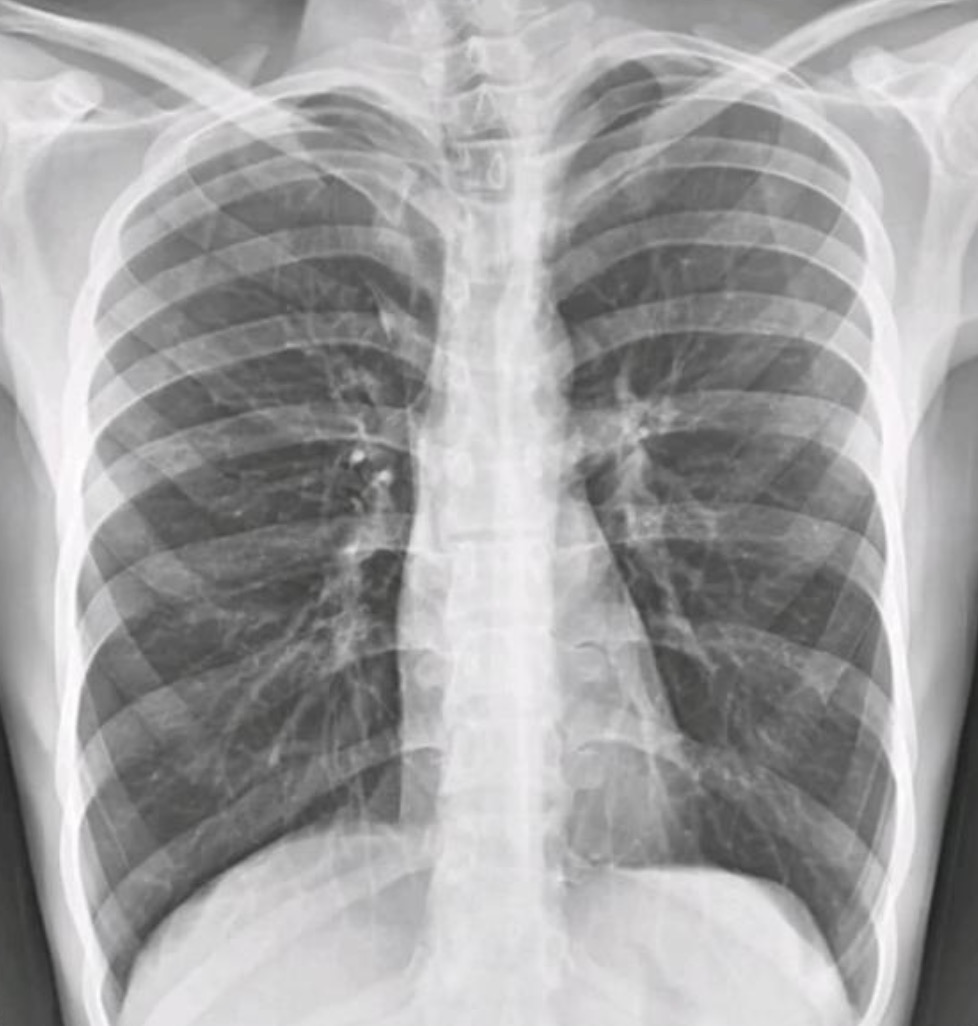

Exemple de condensation avec bronchogramme aérien :

Ici, aucun de ces éléments n'est présent 👉 Le cliché montre au contraire une hyperclarté diffuse des deux champs pulmonaires avec des coupoles basses et des côtes horizontales, en parfait contraste avec l'aspect d'une pneumonie.

Réponse A : Faux. La pneumonie se définit radiologiquement par une condensation alvéolaire systématisée : opacité homogène, à limites nettes, respectant une topographie lobaire ou segmentaire, souvent associée à un bronchogramme aérien (bronches visibles en noir au sein de l'opacité blanche).

Critères radio d'une pneumonie : condensation alvéolaire systématisée, bronchogramme aérien.

À ne pas confondre avec : atélectasie (rétraction), OAP (opacités bilatérales périhilaires), épanchement pleural (ligne de Damoiseau).